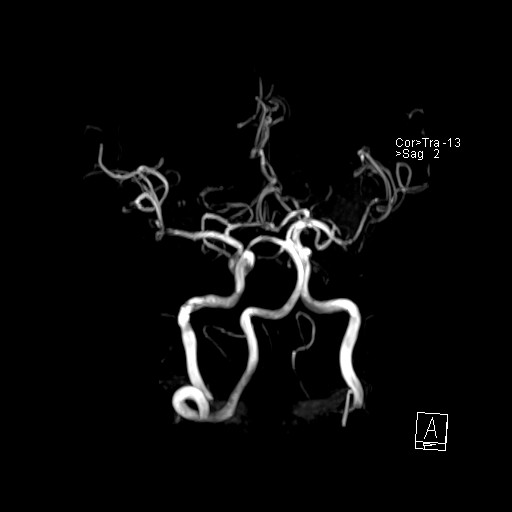

239716 - VILLANUEVA, WILLIAM A. - Number 3 |

|

239716 - VILLANUEVA, WILLIAM A. - Number 3 |